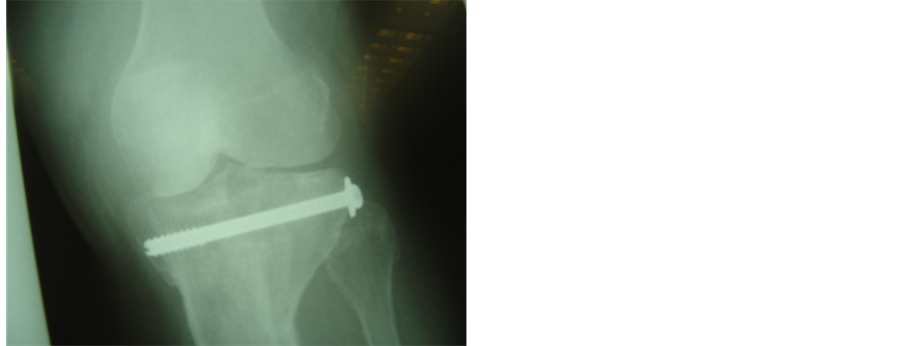

Figure 2. (a), (b): Schatzker IV fracture. Pre operative X-rays AP and Lateral; (c), (d): The fracture was treated with combination of hybrid fixator with one canulated screw. X-rays AP and Lateral three years later before removal of canulated screw.

removed after complete fracture healing was confirmed, both radiologically and clinically. All fractures had united between the 12th and 16th postoperative week, at which time vigorous physiotherapy to achieve full range of knee motion was advised. Patients were usually discharged six months postoperatively.